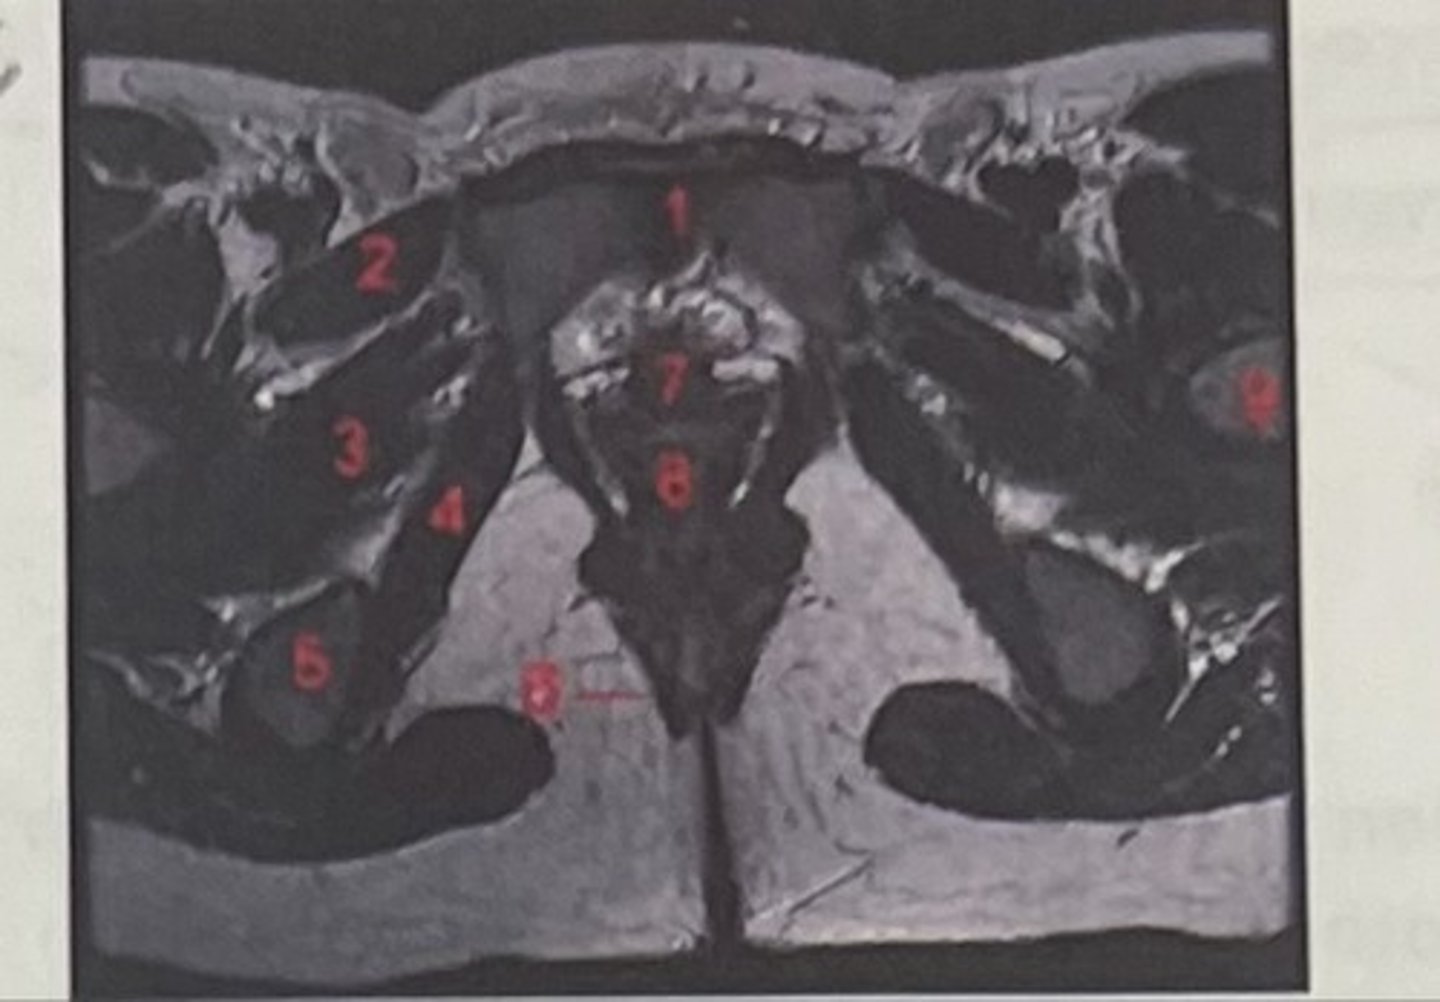

pubic symphysis

What is 1

Pectineus

What is 2

Obturator externus

What is 3

obturator internus

What is 4

ischial tuberosity

What is 5

external spincter

What is 6

Urethra

What is 7

Vagina

What is 8

Femoral nerve

What is 9

Left lung